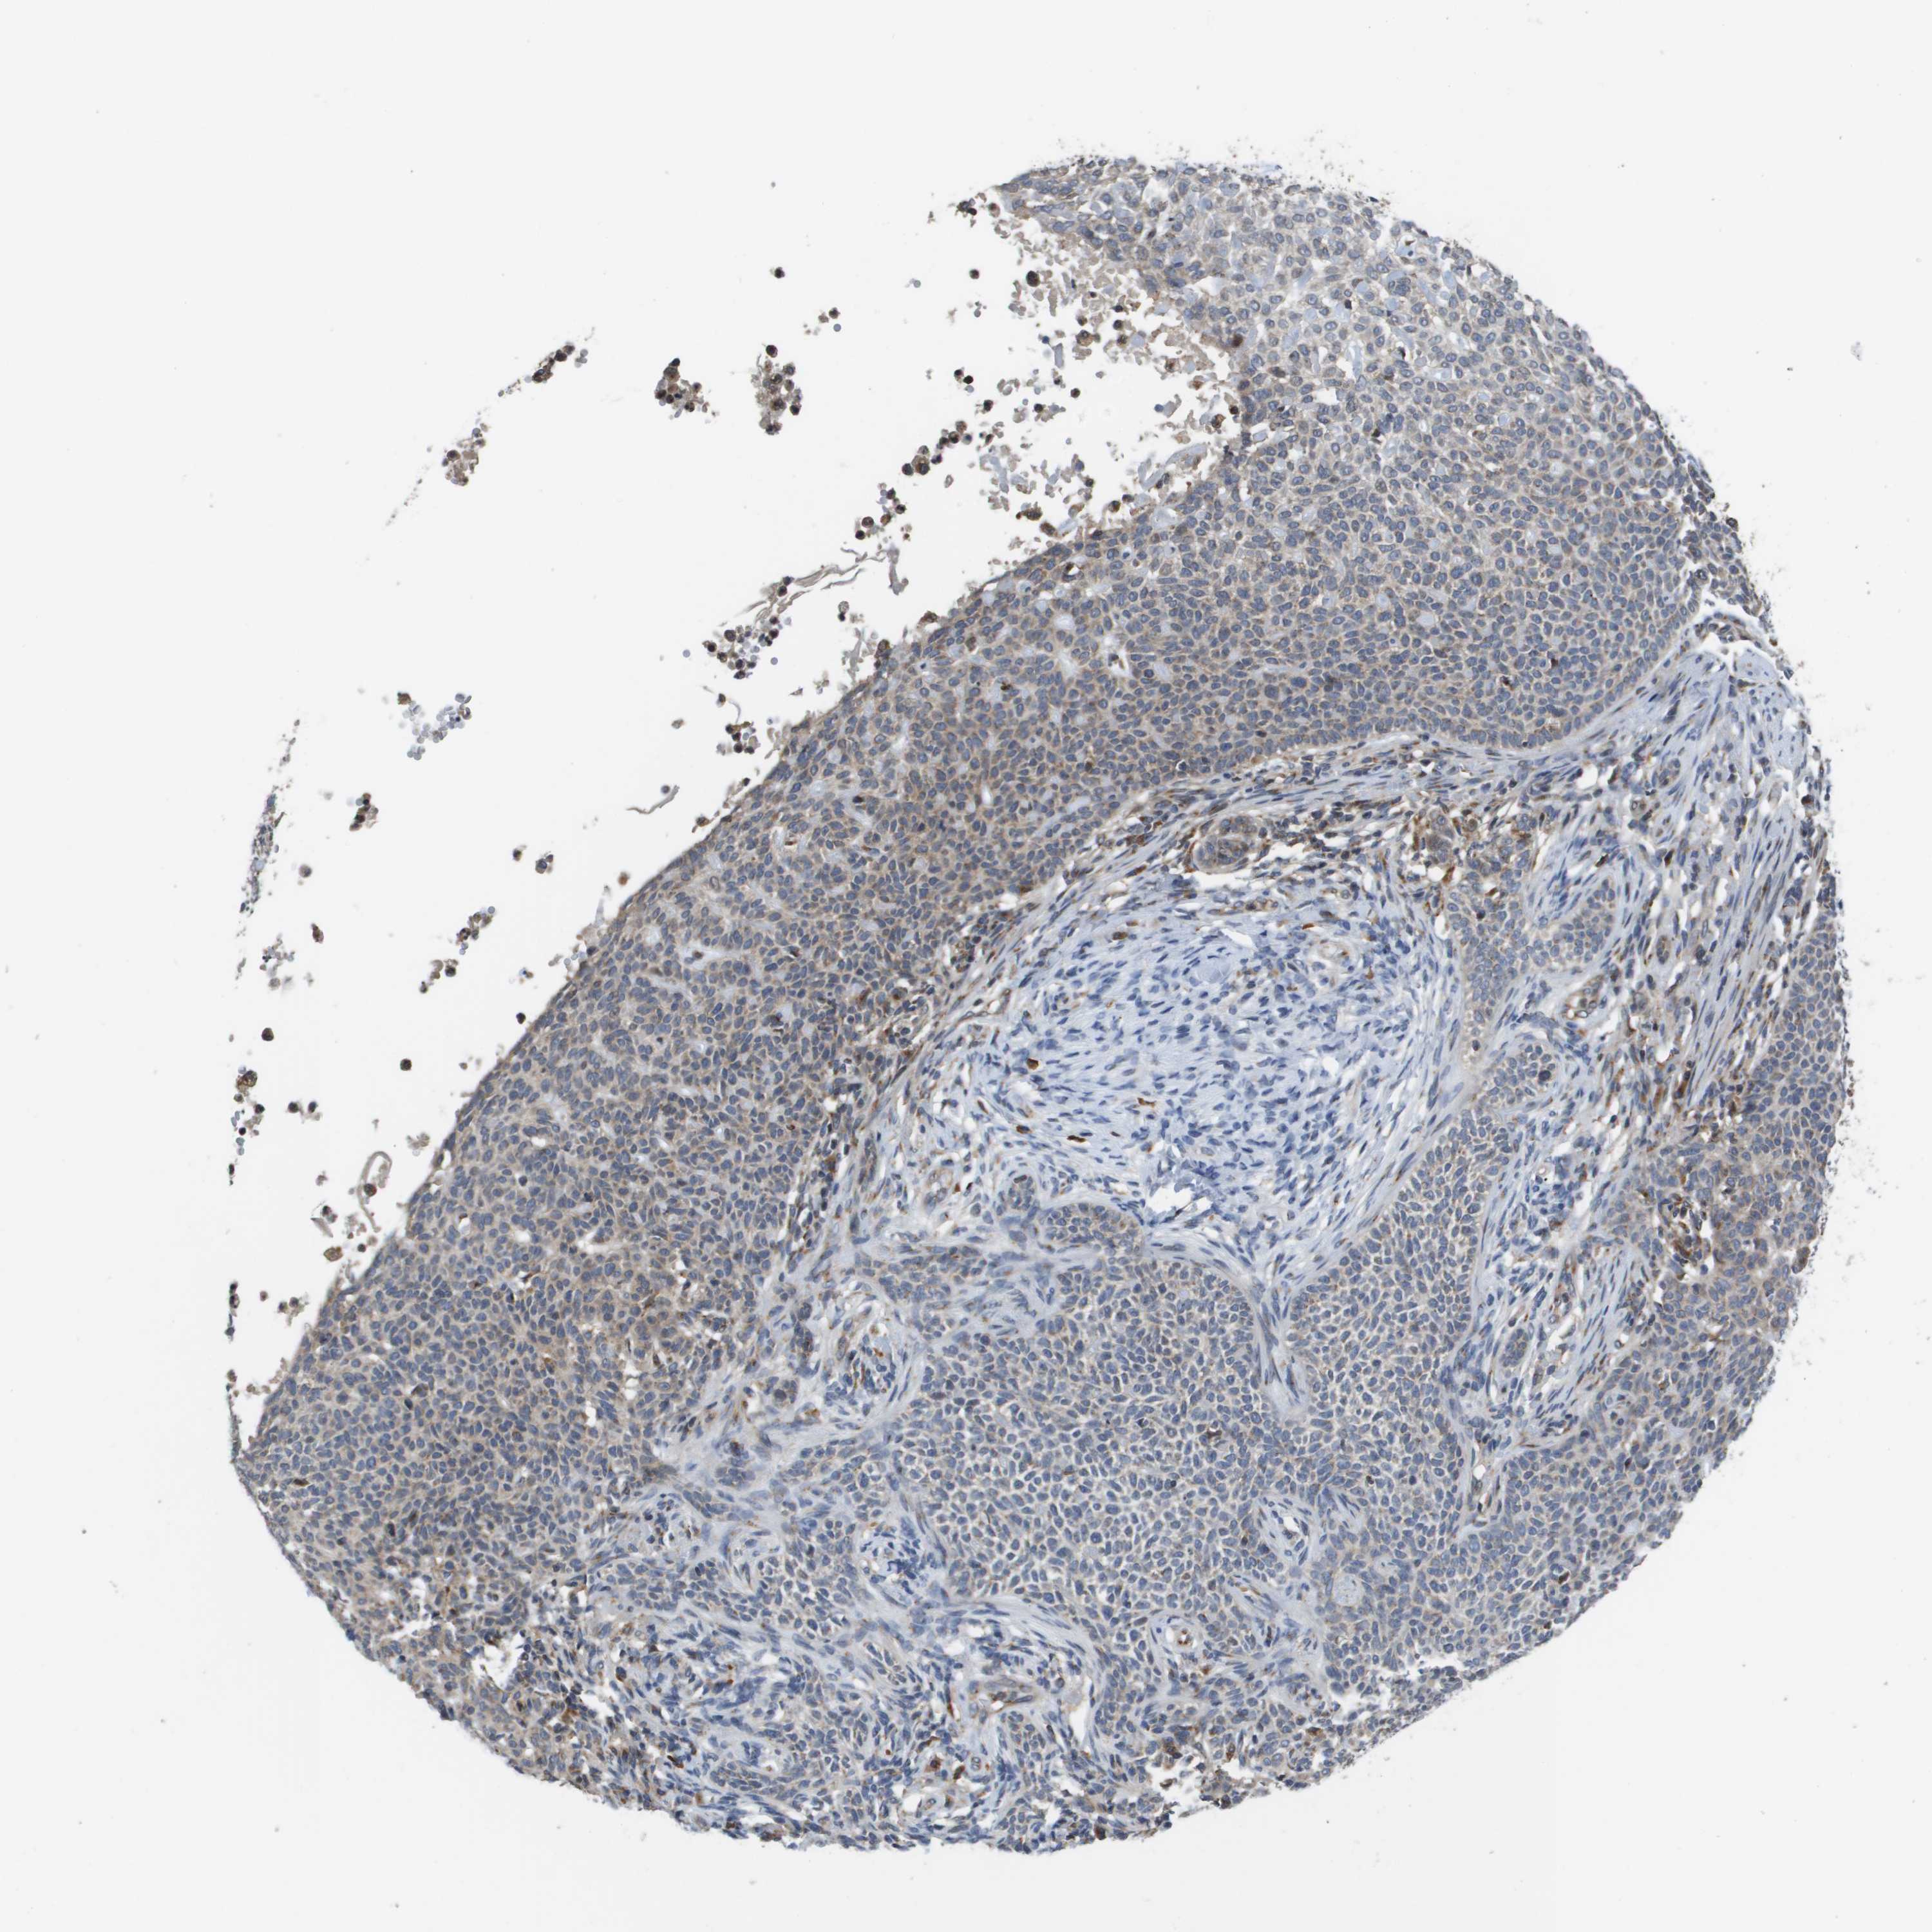

SKIN CANCER - Protein expressioni

A mouse-over function shows sample information and annotation data. Click on an image to view it in a full screen mode. Samples can be filtered based on level of antibody staining by selecting one or several of the following categories: high, medium, low and not detected. The assay and annotation is described here.

Each image is clickable and will lead to virtual microscopy that enables deeper exploration of all samples and also displays staining intensity scores, fraction scores and subcellular localization as well as patient and tissue information for each sample.

Antibody HPA006277

Antibody HPA006507

Antibody CAB017027

Staining

High

Medium

Low

Not detected

Intensity

Strong

Moderate

Weak

Negative

Quantity

>75%

75%-25%

<25%

None

Location

Nuclear

Cytoplasmic/membranous

Cytoplasmic/membranous,nuclear

Squamous cell carcinoma, NOS

Basal cell carcinoma

Squamous cell carcinoma, metastatic, NOS